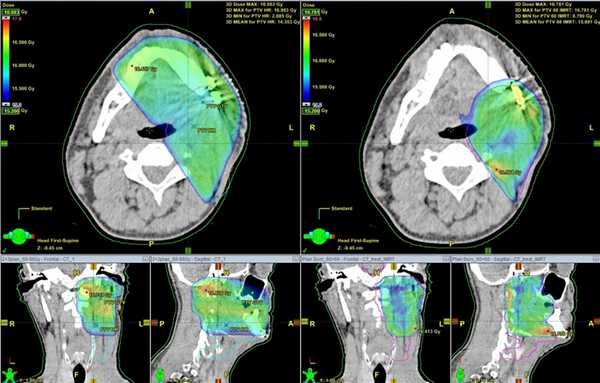

Ниже представлены данные снимков, демонстрирующие более точное распределение дозы в облучаемом объеме и снижение нагрузки на здоровые ткани (IMRT - справа).

Применение модулированной по интенсивности лучевой терапии (IMRT) возможно только при наличии современных линейных ускорителей, систем планирования лучевой терапии, средств для проведения подготовки к лучевому лечению (специализированный компьютерный томограф, фиксирующие устройства и приспособления, магнитно-резонансный томограф) и квалифицированного медицинского персонала. Все это позволяет сделать подход к каждому пациенту индивидуальным, ориентированным на безопасность и максимальный результат за минимальное время. В настоящий момент наша Клиника является единственным в Санкт-Петербурге и Ленинградской области медицинским учреждением, располагающим всем необходимым арсеналом для осуществления данной методики облучения.